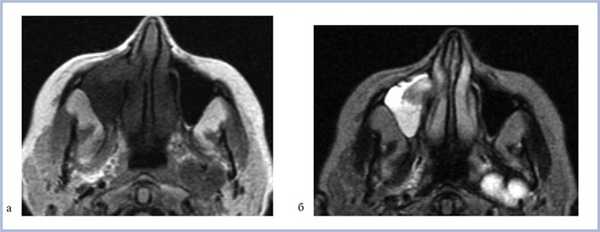

При воспалительных изменениях в ретроантральной жировой клетчатке верхнечелюстной пазухи на РКТ повышаются денситометрические значения ее плотности [10]. При одностороннем процессе отмечается выраженная асимметричность значений плотностей (рис. 4).

Рис. 4. Рентгеновская компьютерная томограмма околоносовых пазух. Аксиальная проекция, костное окно.